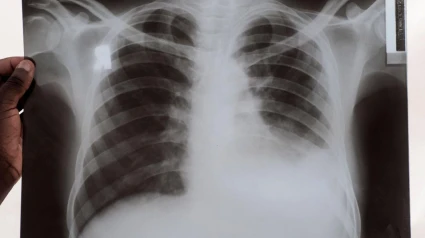

Esta es la enfermedad que podrías padecer y que desconoces: hasta un cuarto de la población es portadora